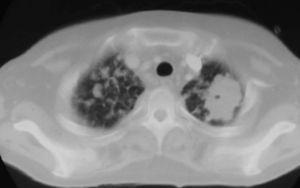

Fig. 3. Tomografía computarizada a la altura de la carina.

Mujer de 34 años de edad, con antecedentes de lupus eritematoso de complicado control que obliga a un tratamiento prolongado con dosis altas de corticoides. Presenta clínica de un mes de evolución de astenia, tos y febrícula con sudoración profusa en los últimos 10 días, que evoluciona con deterioro progresivo y disnea de reposo.